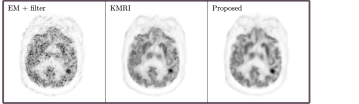

Inspired by the prior arts, here we propose a personalized representation framework for inverse problems in medical imaging. In this proposed framework, the original unknown image 𝒙𝒙\bm{x} is represented by a deep neural network as shown in (4). The prior image of the same patient is employed as network input 𝜶𝜶\bm{\alpha} to construct a personalized representation. The network parameters 𝜽𝜽\bm{\theta} are updated in the inverse-problem optimization process. Compared to employing random noise as network input as presented in [15], using prior images of the patient can make the representation more accurate. To illustrate this, Fig. 1 presents the comparison of network outputs with different network inputs using the brain dataset introduced in Section 3.2. Clearly, when the patient’ own MR image is employed as network input, the cortices regions are clearer and noise in white matter regions is reduced. After substituting 𝒙𝒙\bm{x} with the neural network representation (4), the original data model shown in (1) can be rewritten as

Refer to caption

(a)

Figure 1: One coronal view of the network output by using random noise as network input (left) and using the Patient’s MR image as network input (right). Details of the brain PET-MR data set are introduced in Section 3.2